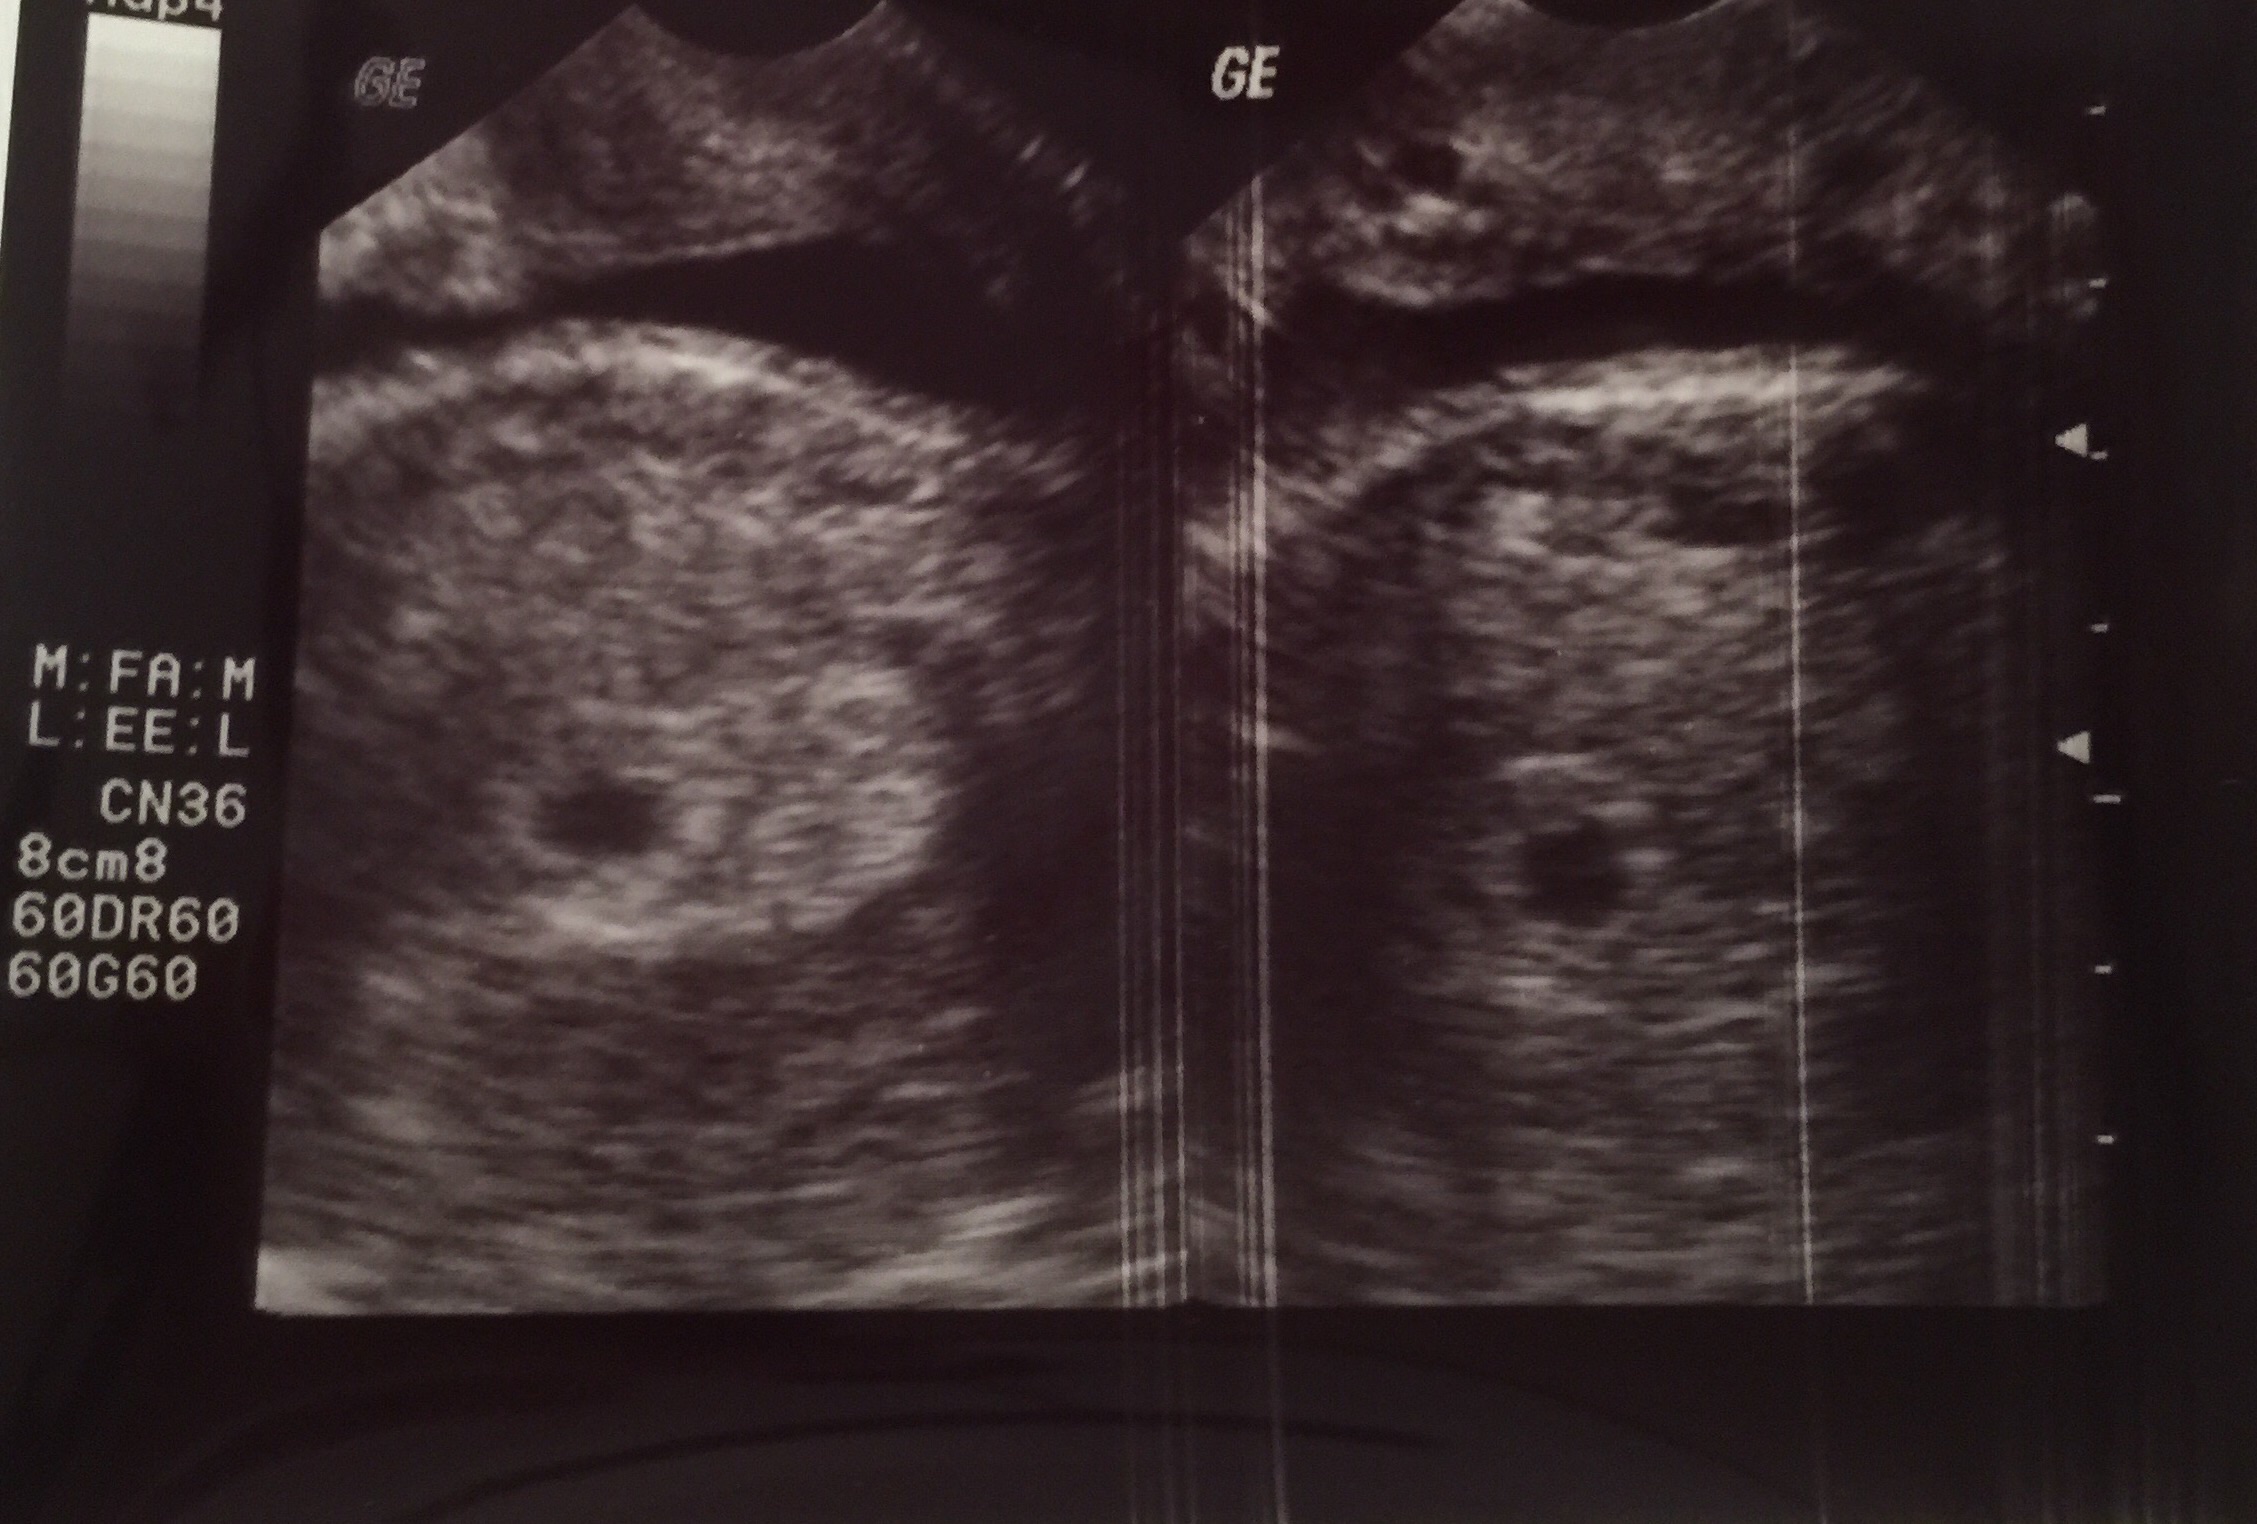

Heard our twins' heartbeats today. It feels so surreal!! Then the doc said uh-oh....there's a third sac! Unbelievable! No heartbeat but it definitely has us on the edge of our seats!